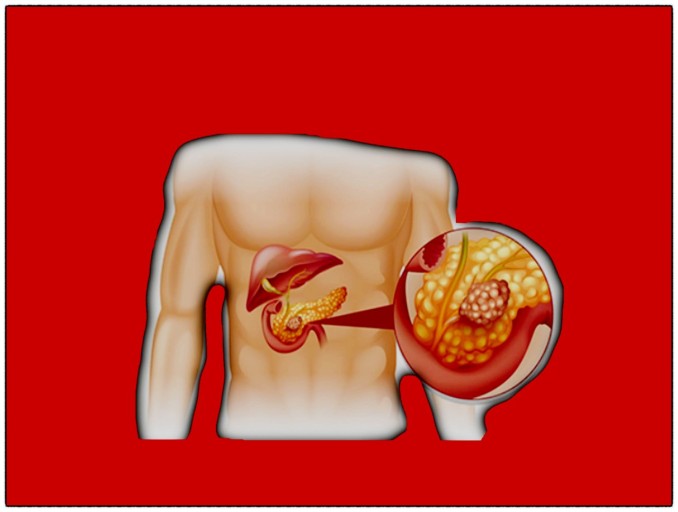

그중에서도 조기 발견이 특히 어려운 질환이 바로 췌장암입니다.췌장은 우리 몸 깊은 곳에 위치해 있어 증상이 생겨도 다른 질환으로 착각하기 쉬운데요,

- 췌장은 복부 깊숙이 위치해 있어, 암이 생기면 복부나 등으로 통증이 퍼집니다.

- 특히 음식 섭취 후 심해지는 경우, 단순한 소화불량으로 오인되기 쉬워요.

- 깊고 둔한 통증이 등쪽까지 방사된다면 의심이 필요합니다.